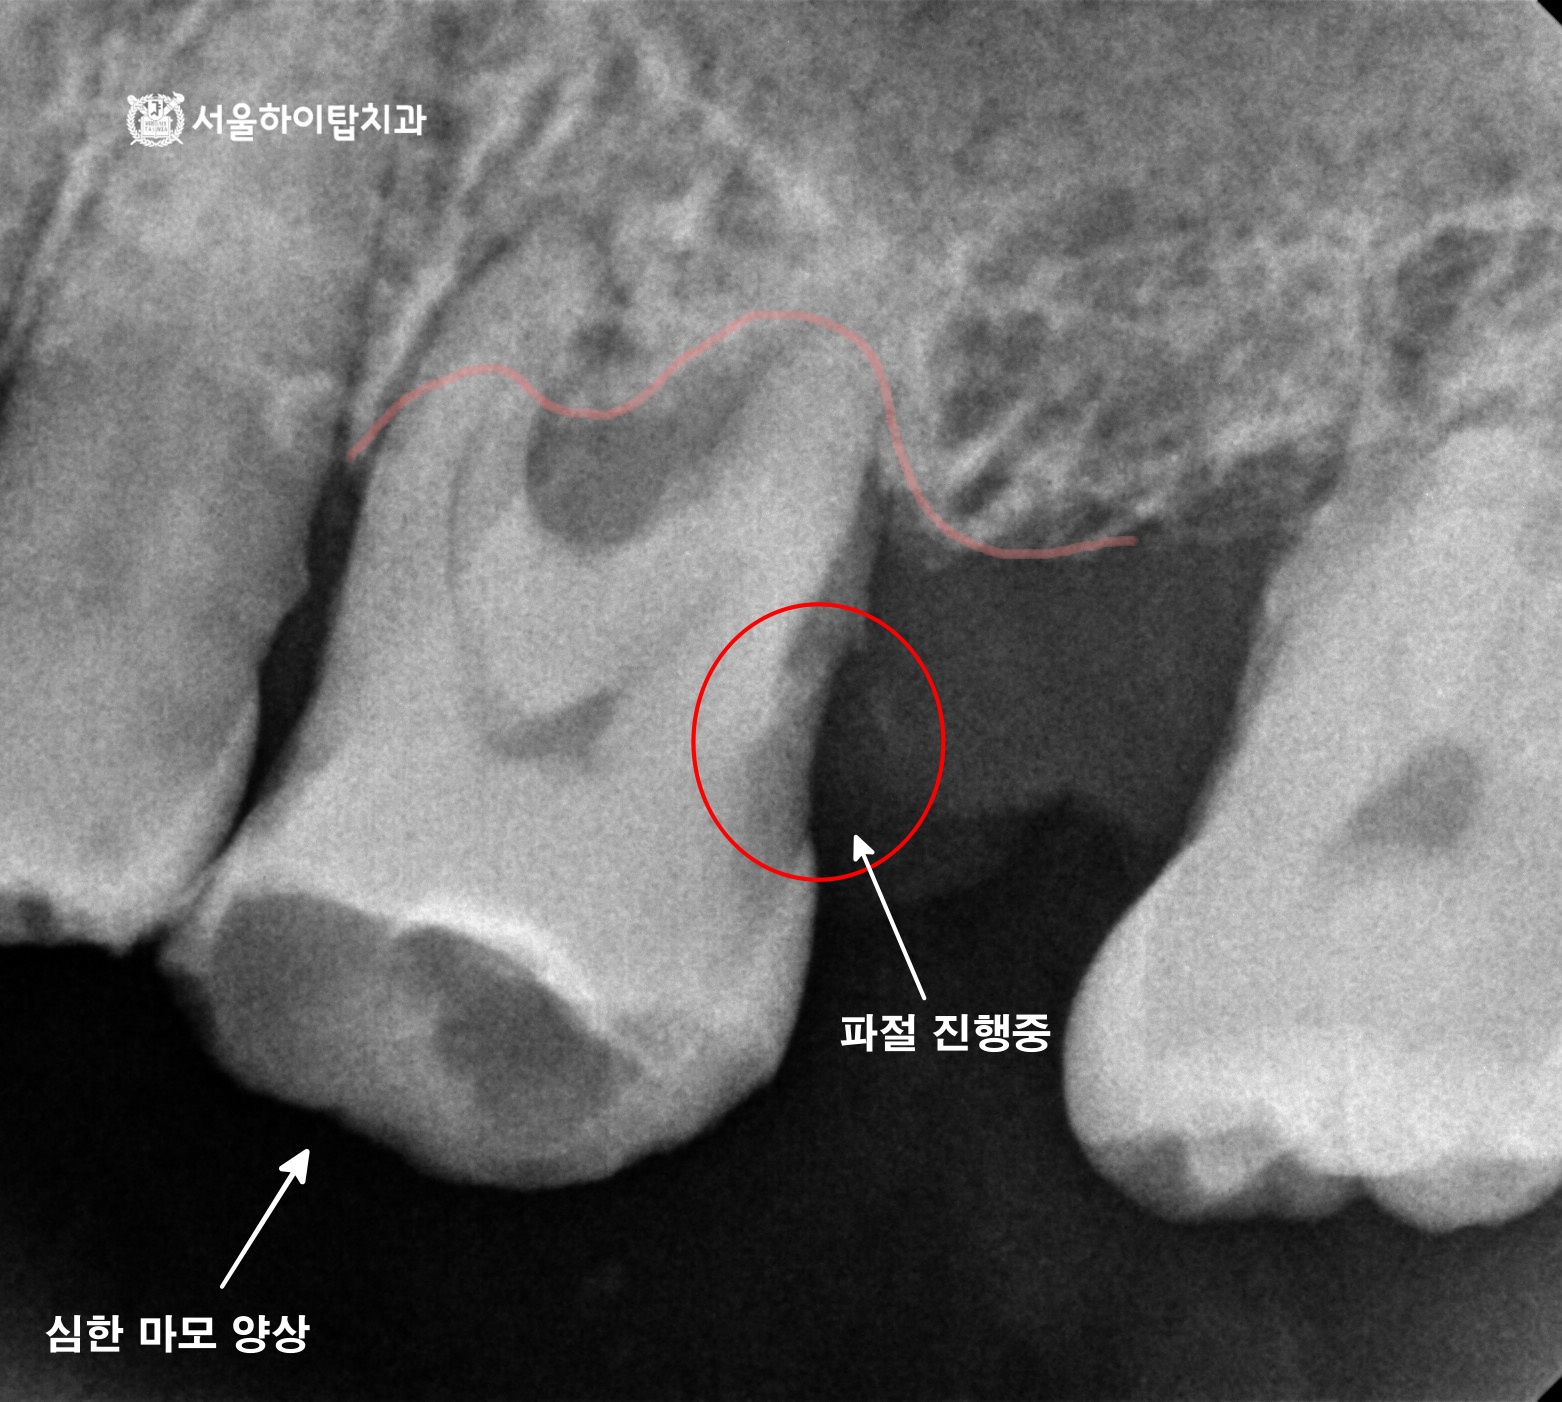

십정동 치과 어금니 상실 후 CT 기반 정밀 진단 후 진행한 당일 즉시 임플란트 진행 과정 동암역 치과, 불편한 앞니 바로 신경치료할까요? 검사부터 치료까지 (치근단 염증 · PFM 크라운) 주안역 치과 치아 흔들림(동요도 3도) 발치 후 임플란트 진행 과정 부평 치과 치아 머리·목 부분에 진행된 충치, 신경치료 과정 및 장기적 파절 가능성 안내 십정동 치과 앞니에서 파절이 쉽게 일어나는 부위가 있다? 절단연 파절 후 레진 수복 과정 간석오거리역 치과 치수까지 침범한 충치, 발치 후 임플란트 진행 과정 (정기검진과 조기 치료의 중요성) 만수동 치과 80대 고령환자, 심한 충치 치아 발치 후 임플란트 수술 과정 (발치가 필요한 충치?) 백운역 치과 신경치료 후 앞니 치아가 파절되기 쉬운 이유가 무엇일까? 임플란트 수술 과정 주안동 치과 70대 고령 환자│뿌리까지 이어진 치아 파절의 원인과 임플란트 수술 과정 간석동 치과│치주염으로 인한 골 흡수와 치아 흔들림, 뼈 이식을 동반한 임플란트 치료 과정 부평 치과 심한 치아 통증 엑스레이에서 보이지 않는 치수염? 신경치료와 크라운 수복 과정 만수동 치과|성장기 치아 상실, 왜 성인이 되어 임플란트를 했을까요? (상악동 거상술 동반) 십정동 치과 상실된 치아가 불러오는 연쇄적 문제? 치조골 흡수와 기울어진 어금니, 뼈이식 동반 임플란트 과정 동암역 치과 : 균형 잡힌 저작이 중요한 이유, 전반적으로 손상된 치아 및 잇몸 임플란트를 통해 저작 기능 개선 간석역 치과 치주염으로 인한 치조골 흡수, 치아 파절 및 마모까지 임플란트 가상 시뮬레이션을 통한 안전한 수술 과정 1 2 Next Archives 2026년 4월 2026년 3월 2026년 2월 2026년 1월 2025년 12월 2025년 11월 Categories 미분류 신경치료 심미 치료 임플란트 BACK TO TOP